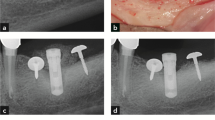

Radiographical analysis

Periapical X-rays were taken during each visit of the study to assess bone loss and progression of the peri-implantitis (Fig. 4). Interproximal bone levels were measured at each implant, from the implant shoulder to the first visible bone to implant contact. The mean radiographic bone level was calculated averaging the mesial and distal measurements. All radiographs were measured by the same calibrated examiner (J.S.) using a computer image analysis software (Image J., National Institutes of Health, Bethesda, MD) after calibrating the images using the previously known distance (length of the implant) to compensate for image distortion and magnification.

Radiographic assessment. a Baseline visit, 3 months after implant placement. Ligatures were placed during this visit. b 1 month after ligature placement. Change of ligatures. c 2 months after ligature placement. Change of ligatures. d 3 months after ligature placement. Change of abutments and change of ligatures. e 4 months after ligature placement, 1 month with platform-matching abutments. Ligatures were removed in this visit. f 8 months after ligature placement visit, 4 months after ligature removal

Radiographic analysis

A progressive increase in radiographic bone loss was observed all over the experimental peri-implantitis experiment. At the end of the induction, bone loss in the test group was 2.53 ± 0.39 mm, while in the control group, it was 2.55 ± 0.30. Bone loss developed during the progression phase, although the change was less marked (test: 0.21 ± 0.32 mm vs. control: 0.15 ± 0.3 mm). The higher increase in bone level change (bone loss) was observed in the test and control groups between the third (1.94 SD = 0.23 vs. 1.94 SD = 0.26 mm respectively) and the fourth month of the induction period (3.00 SD = 0.35 vs. 2.87 SD = 0.26 mm respectively); it coincided with the abutment change (Fig. 4). Once ligatures were removed, radiographic bone loss continued, but to a slower pace, being approximately 35% of the implant surface bone loss in both groups (Table 4). The only statistically significant difference between groups was observed at the baseline visit, with test implants showing slightly higher bone remodeling than control implant (0.47 SD = 0.09 vs. 0.32 SD = 0.16 mm respectively), although these differences do not have any clinical relevance.